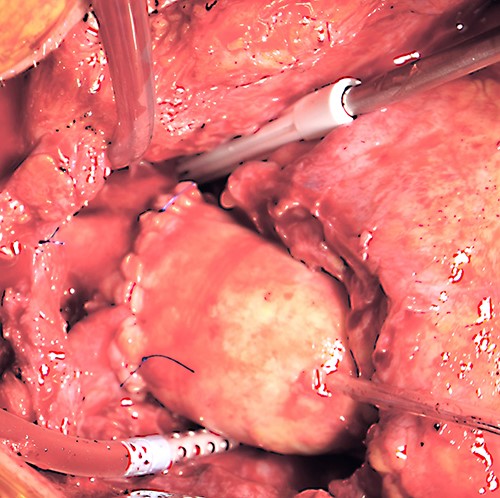

At almost 6 years after the initial surgery, the patient was transferred to our unit with a chronic sternal fistula. The computed tomography (CT) scan showed almost complete destruction of the manubrium sterni on the left side, a fistula path into the anterior mediastinum and an abscess collection around the ascending aorta (Fig. 1). The echocardiography ruled out any significant valve regurgitation or stenosis, endocarditis or aortic root abscess. Pseudomonas aeruginosa was cultivated from the fistula.

Preoperative thoracic CT scan; (A) image indicates the sternal defect caused by osteomyelitis and the infected hematoma surrounding the native aortic arch; (B) topogram indicating the sternal defect caused by osteomyelitis in coronary sectional plane; (C) image indicates the sternal defect caused by osteomyelitis and the infected hematoma surrounding the aortic prosthesis.